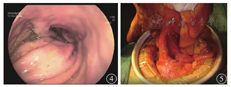

患者男,56岁,因"反复腹胀伴恶心、呕吐6个月"于2018年6月18日入住哈尔滨医科大学附属第一医院。患者6个月前无明显诱因出现腹部胀痛,以脐周为主,无放射痛,伴恶心、呕吐,呕吐物为黄绿色水样物,同时肛门排气减少。对症治疗后症状好转。2018年5月患者再次出现上述症状,发作时排气减少,呕吐胃内容物后症状可缓解。自行购买益生菌、中药服用半个月后自觉好转。2018年6月11日患者出现相同症状,恶心、呕吐较前加重,呕吐物为食物伴有胆汁。6月14日于当地医院行胃肠镜检查,诊断为胆汁反流性胃炎,给予相应治疗后未见好转,腹胀加重,排气、排便消失。6月18日急诊入住哈尔滨医科大学附属第一医院,考虑肠梗阻,入院时体格检查示无欲貌,意识不清,慢性病容,血压为98/62 mmHg(1 mmHg=0.133 kPa),心率为100次/min,腹部饱满,腹部叩诊呈鼓音。给予胃肠减压、禁食水、补液、营养支持治疗。6月23日患者视物重影,目光呆滞;25日出现嗜睡症状,病情进行性加重;27日因晕厥转入重症监护病房,给予气管插管、抗炎、对症支持治疗。2018年7月5日行头颅MRI检查,确诊韦尼克(Wernicke)脑病;7月9日行腹部CT检查见右侧肠管扩张、积气、积液,左中下腹局部肠系膜旋转(图1)。腹部计算机断层扫描血管造影(computed tomography angiography, CTA)检查见肠系膜上动脉及其分支移位、旋转(图2)。神经内科和普外科会诊后建议经口置入肠梗阻导管,经肠梗阻导管注入少量流食,口服肠道益生菌,辅以胃肠黏膜保护剂,补充维生素B1、B6,纠正电解质紊乱,以及充分静脉营养支持等治疗。2018年8月10日患者腹胀减轻,无恶心、呕吐,有自主排气、排便,意识好转,给予经口半流质饮食;半流质饮食6 d后患者腹胀加重,伴恶心、呕吐,呕吐物为胆汁,排气、排便消失。回顾病史,患者住院期间反复多次出现禁食数日后症状减轻,半流质饮食数日后症状加重。2018年8月16日行直立位上消化道造影检查示近段空肠扩张,呈螺旋状,可见液气平面,动态观察可见肠管逆蠕动(图3)。小肠镜检查可见距幽门40 cm处小肠走行扭曲,呈"S"形,其口端肠腔明显扩张、绒毛结构变平、环形皱襞消失(图4)。患者于2018年9月24日行腹腔镜下小肠切除吻合术治疗,术中见近段小肠和肠系膜血管顺时针旋转(图5),远端梗阻扩张空肠位于肠管穿入肠系膜处,由对侧小肠系膜穿出,延续至回盲部,术中诊断为中肠旋转不良。2018年11月20日患者恢复良好而出院。

影像学检查对中肠旋转不良的诊断至关重要。多普勒超声检查对诊断中肠旋转不良具有一定价值,扩张的肠管和肠系膜上静脉以顺时针方向缠绕肠系膜上动脉,扭曲的肠系膜血管构成了漩涡符号,这是典型的旋转不良,甚至肠系膜上静脉反转至肠系膜上动脉的左侧,多普勒超声检查可以清晰地显示该现象[1,5]。腹部CTA成像同样可以清楚地显示肠系膜血管旋转情况,如本病例所示。腹部CT检查显示的漩涡征即螺旋状的肠系膜血管,这种体征并不是特异性的,也可能会在脾脏扭转等其他病理情况下出现。但腹部CT检查可以显示空肠扩张、积气、积液,提示梗阻和显示梗阻部位。据报道,上消化道造影检查判断中肠扭转的准确度为100%[6]。X线动态观察造影剂的通过情况可发现空肠蠕动异常,进而判断空肠梗阻的位置。本病例中,造影剂到达扩张的空肠时明显被稀释,说明空肠梗阻上方有积液,同时该位置的肠管出现逆蠕动现象,这样可以基本明确空肠异常旋转的存在和梗阻的位置。小肠镜检查的优势是可以在直视下进一步判断梗阻是器质性病变还是异常旋转,为手术提供直接证据,本病例经口小肠镜检查可见近段空肠走行扭曲。因此,上消化道造影和小肠镜检查在中肠旋转不良的诊断中具有非常重要的价值。